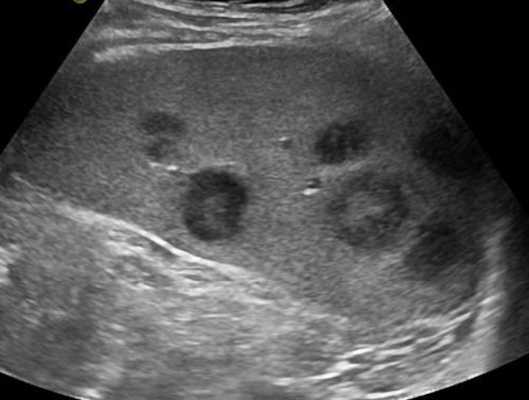

Изменения лимфоузлов на УЗИ при злокачественных новообразованиях

В ходе УЗИ ЛУ можно заподозрить наличие у исследуемого опухоли с агрессивным течением. Выявить прорастание последней или метастазы в лимфоузлы с помощью пальпации невозможно. Благодаря неинвазивности, высокой информативности и доступности, ультразвуковое сканирование является методом скрининга как при первичной диагностике злокачественных процессов в крови, лимфе, внутренних органах, так и у больных после оперативного лечения и/или химиотерапии.

УЗИ с допплерографией у пациентов онкологического профиля показывает следующие нарушения в строении ЛУ:

- увеличение в размерах - обычно до 6-6,5 см;

- шарообразную деформацию или неправильные контуры;

- спаянность в виде конгломератов;

- отсутствие дифференциации на кору и ворота;

- неоднородность структуры с зонами повышенной и пониженной эхогенности;

- жидкостные включения и кальцинаты;

- усиленный кровоток и образование новых сосудов (ангиогенез).

Указанные изменения на снимках чаще обнаруживают при лимфоме.